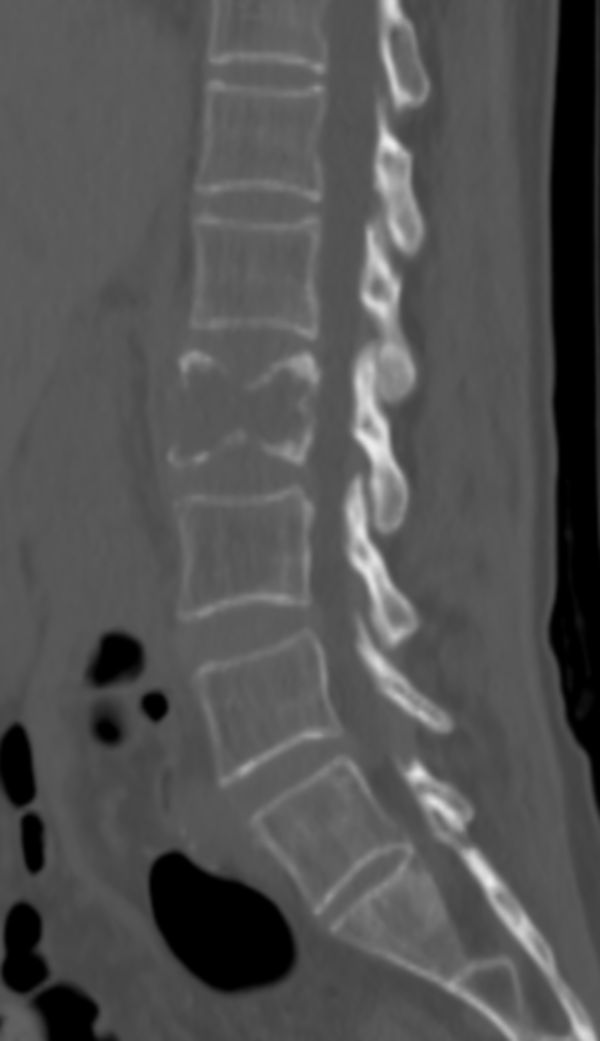

文章配圖

△ 術前CT:腰2椎體骨質破壞,伴周圍軟組織腫脹,考慮骨轉移瘤。